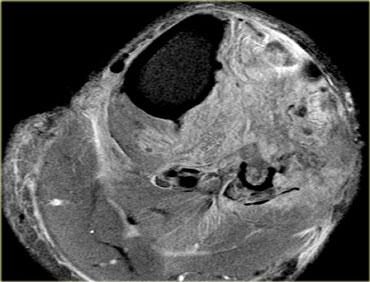

Hình ảnh T1W bên trái của bệnh nhân một tháng sau chấn thương.

Trên hình ảnh sau tiêm Gadolinium, có thể thấy hoại tử ở khoang trước và khoang ngoài.

Khoang sau bình thường.